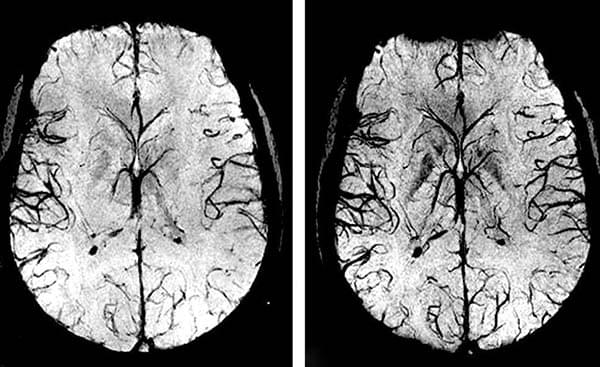

• Zerebrovaskuläre Erkrankungen. Es handelt sich um eine Unterbrechung der Blutgefäße im Gehirn, die zu einer mangelnden Versorgung der Gehirnzellen und damit zu einer Schädigung der Gehirnsubstanz führt. Dies führt häufig zu einem Schlaganfall, der zum Tod oder zu Behinderungen führt.

Wenn die Blutgefäße des Herzens (Koronararterien) durch Cholesterinablagerungen verstopft sind, verursacht dies zunächst Angina pectoris, kann dann aber zu einem Herzinfarkt führen. Und Blutgefäße, die an Kapazität verloren haben und das Gehirn nicht mehr richtig mit Blut versorgen, sind ein sicherer Weg zum Schlaganfall.